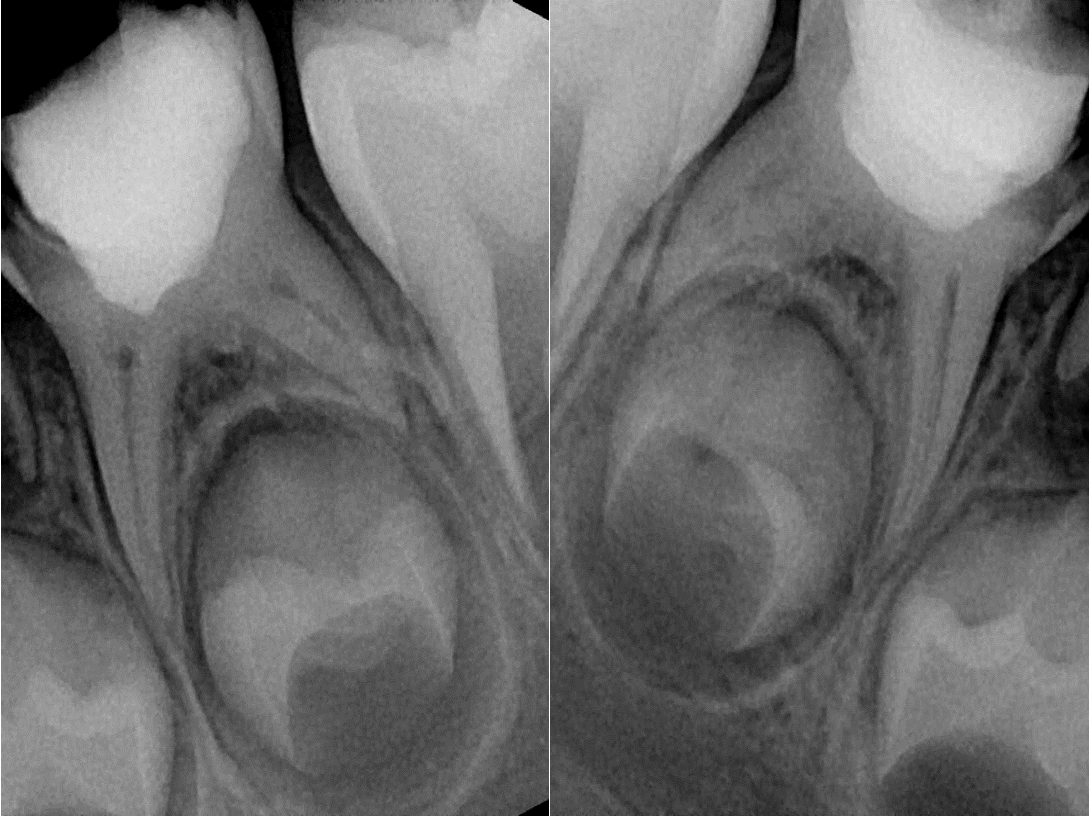

Карієс несформованих постійних зубів, лікарська тактика. Глибокий карієс чи зворотній пульпіт. Вітальна терапія пульпи

– Демонстрація та практика – вітальна пульпотомія, при лікуванні незворотного пульпіту тимчасового зуба.